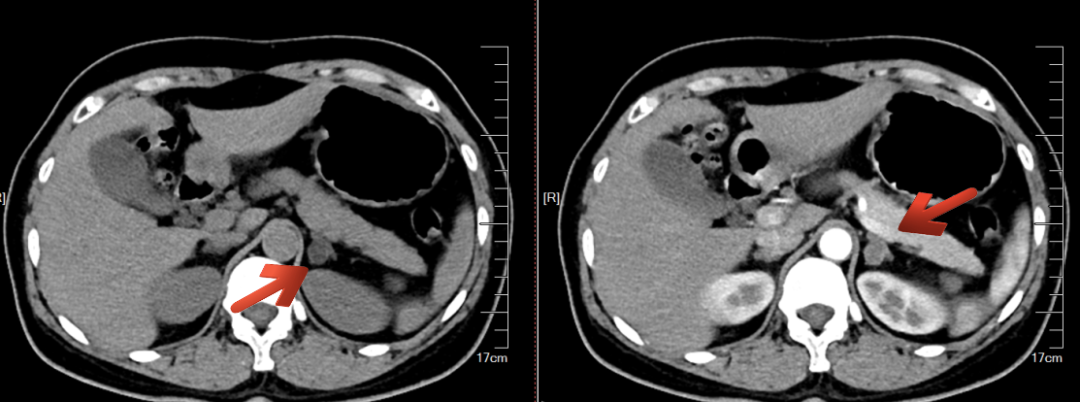

为了解决这个问题,昆山市中医医院MDT团队的血管外科团队亮相,对孙女士进行了双侧肾上腺采血术(AVS),检测了激素分泌情况,终于明确了左侧肾上腺为优势侧,诊断为醛固酮瘤,正是孙女士高血压、低血钾的元凶。

图片